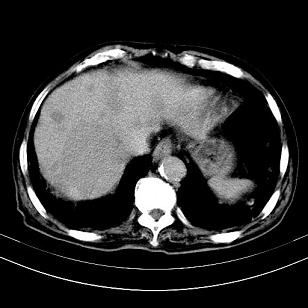

标题: CT19407:肝内还是肝外原发性肿瘤??

男,63岁,高血压病史40余年,

考虑右肝后叶肝癌伴多发肝内转移

考虑右肝后叶肝癌(部分外生)伴肝内多发性转移;右侧肾上腺区恶性肿瘤并肝转移待排。

考虑右肝后叶肝癌(部分外生)伴肝内多发性转移

考虑右肝后叶肝癌(外生型)伴肝内转移。

考虑右侧肾上腺肿瘤并肝内多发转移。右侧肾上腺呈“八”字形,包括内侧枝及外侧枝,内侧枝受压,考虑外侧枝原发肿瘤。”

考虑肝右后叶肝癌(部分外生)伴肝内多发性转移;不排除右侧肾上腺区恶性嗜铬细胞瘤并肝转移。